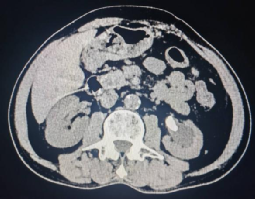

术前影像学检查: